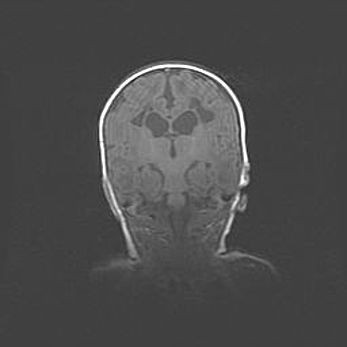

Наружная гидроцефалия с возможной атрофией височных областей.

Возраст: 28 дней

Вес: 3670 г

Пол: мужской

Окружность головы: 38 см

Срок гестации: 40 недель

Гидроцефалия головного мозга у новорожденных – это заболевание, которое характеризуется скоплением избыточного количества спинномозговой жидкости в желудочковой системе головного мозга в результате затруднения её перемещения от места выработки к месту поглощения в кровеносную систему или вследствие нарушения абсорбции. При открытой наружной форме гидроцефалии у новорожденных расширяются и переполняются субарахноидные пространства.

При нормотензивных  формах,  которые,  как  правило,  являются  следствием  перенесенных ишемических  повреждений  паренхимы  мозга,  возможно  сочетание микроцефалии  с нормотензивной гидроцефалией. В основе данных изменений лежит атрофия больших полушарий с преимущественной  локализацией  в  лобно-височных  областях.